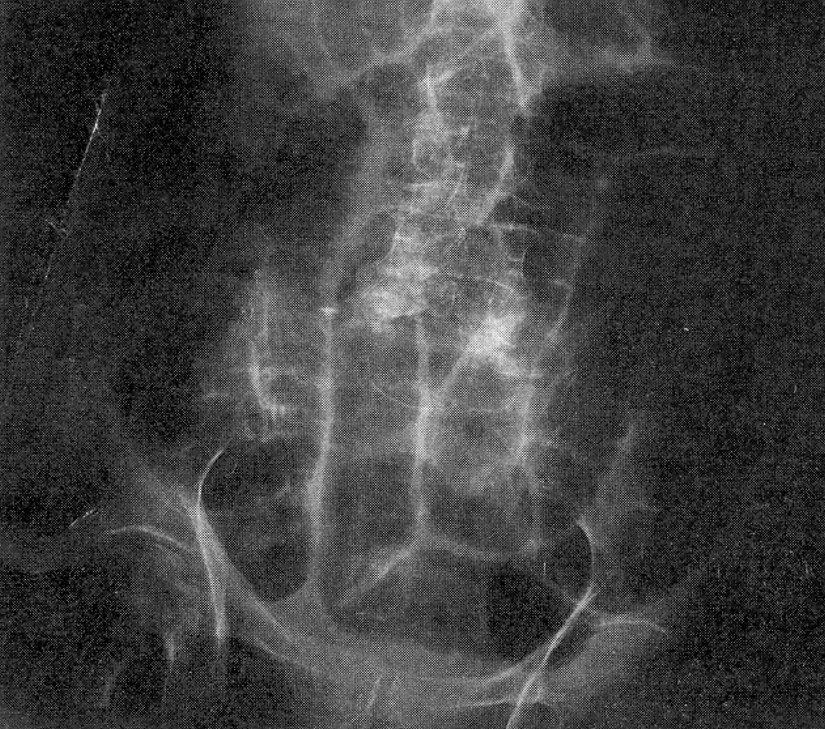

Because of the COVID19 pandemic, you are practicing medicine by telemedicine. You are shown the abdominal x-ray of a 102-year-old woman and are told she presented with a 2-day history of abdominal pain and distension, recurrent emesis, and pain radiating down her right medial thigh to her knee.

DIAGNOSIS: Strangulated obturator hernia (OH).

Because of their wide pelvis and the unique shape of their obturator canal, OHs are more common in women - partcularly those that are thin and elderly and/or multiparous. The patient may be asymptomatic, or, as was true in the mystery case, present with symptoms and signs of intestinal obstruction. Compression of the obturator nerve may cause a "burning" neuropathic pain or numbness radiating from the groin to the median thigh and the knee (Howship-Romberg sign). Physical exam may reveal fullness in the femoral triangle and hypo- or hyperalgesia along the path of the obturator nerve. In women, the hernia may be detectable on pelvic examamination. The diagnosis is best confirmed with a pelvic CT scan, although ultrasound may also reveal the hernia. The treatment is surgical.